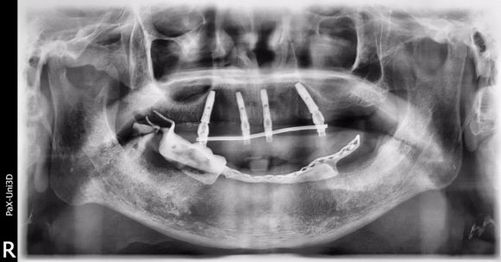

【种植后x线片】